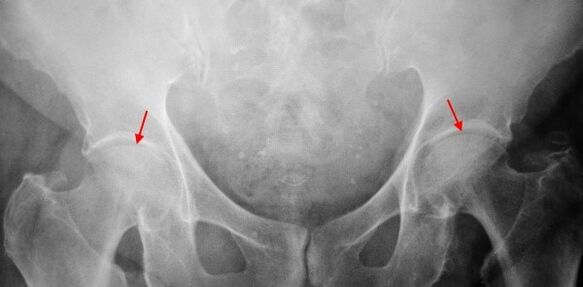

Mild changes are determined in the X scrubbing of a patient with a 1st degree coxartrosis: moderate uneven narrowing of the joint and growth of bones around the outer or inner edge of the acetabulum, in the absence of the femur head and neck.

For X -Ray images, a significant narrowing of the joint gap (more than half of the normal height) is determined for coxarthrosis.The femur head is slightly upward, deformed and increased in size, and the contours become uneven.Bone growth, with this degree of coxarthrosis, appears not only on the outer edge of the internal but also on the outer edge of the acetabulum and goes outside the cartilage.

X -rays at 3 degrees Coxartrosis are sharp reducing the joint gap, outstanding expansion of the thigh head and multiple bone growth.

Diagnosis of coxarthrosis is based on the clinical symptoms and data of further tests, which are most important to radiography.In many cases, X rails allow not only the degree of coxarthrosis but also the cause of its occurrence.Thus, for example, the growth of the cervical-diaphragm angle, the flattening of the scenes and the acetabulum indicate dysplasia, and changes in the shape of the proximal part of the femur indicate that coksartrosis is a consequence of pertes disease or youth epiphyolic.X -rays of patients with coxarthrosis can also be detected to indicate injuries.